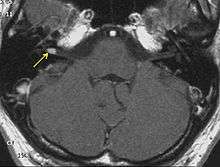

Advances in scanning and testing have made possible the identification of small acoustic neuromas (those still confined to the internal auditory canal). Magnetic resonance imaging (MRI) using Gadolinium as an enhancing contrast material is the preferred diagnostic test for identifying acoustic neuromas. The image formed clearly defines an acoustic neuroma if it is present and this technique can identify tumors measuring down to 5 millimeters in diameter (the scan spacing).

When an MRI is not available or cannot be performed, a computerized tomography scan (CT scan) with contrast is suggested for patients in whom an acoustic neuroma is suspected. The combination of CT scan and audiogram approach the reliability of MRI in making the diagnosis of acoustic neuroma.[8]